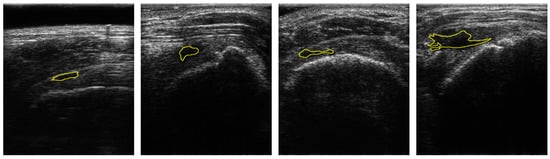

Figure 1 shows the samples of acquired images. To annotate the datasets, the acquired US images were devided into two classes: Class-0 and Class-1. Class-1 indicates the regions of RCTs which include all objects except for the RCT regions. Annotations were confirmed by two professional orthopedic doctors. However, the datasets for RCTs are imbalanced because the regions of the RCTs were small within the field of view (FoV) of the ultrasound images. Figure 1 shows the distribution of the RCT regions corresponding to the US images. This demonstrates that the dataset is imbalanced with the small area of the RCTs. The term sparse is utilized to indicate the small number of pixels in RCTs whose area is smaller than the background area, and thus the RCT (Class-1) is a sparse set of hard examples [21]. Therefore, the imbalanced training with an imbalanced dataset can degrade the performance of the deep learning algorithm in the segmentation of the RCT since the optimization of the network is biased toward one class [21,22]. Since the number of pixels of the background are much higher than that of RCTs, Class-0 is considered to be an easy case while Class-1 is considered to be a difficult case [21].

Figure 1.

Samples of US images and the ground truths of Rotator-Cuff Tears. The ground truths are overlaid as a yellow line. Using the system of which pitch size is 0.3 mm, aperture size is 4 mm × 38 mm, capable frequency is 5 to 14 MHz, and imaging frequency for the clinical experiment is 13.3 MHz.